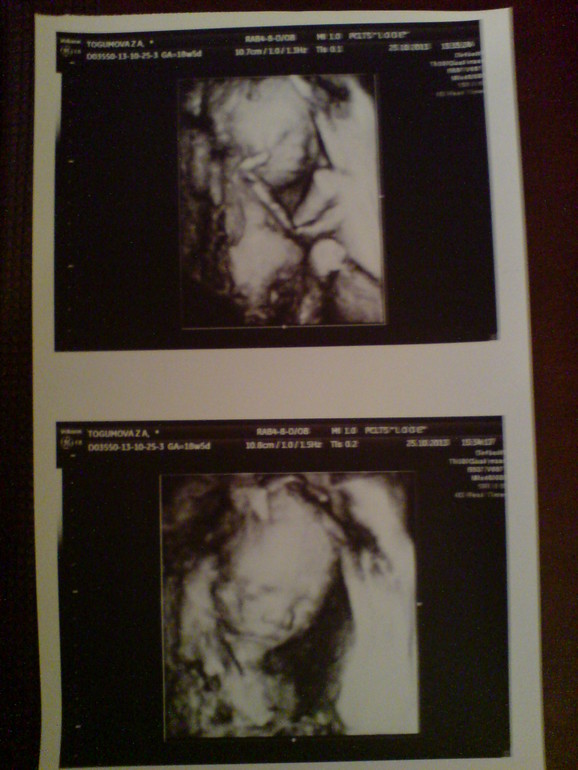

И тадаааам,вот и моя сладкая девочка,у которой что-то нос картошкой,ну да ладно

(фотографии с экрана монитора и с распечатки) ПОДКАТ